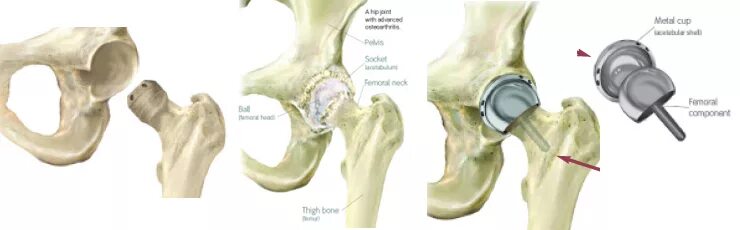

Срок службы тазобедренного эндопротеза